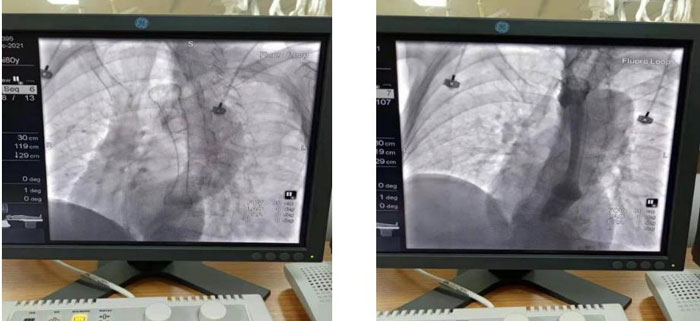

患者于2021年12月15日行“食管球囊擴(kuò)張+食管支架植入術(shù)”。術(shù)中在數(shù)字減影X光機(jī)透視下準(zhǔn)確定位示狹窄位于食管胸中段,長約6CM,管腔極度狹窄,僅少量造影劑呈線型通過,鉛標(biāo)標(biāo)記狹窄遠(yuǎn)近兩端;導(dǎo)絲引導(dǎo)下經(jīng)口、食道引入5f造影導(dǎo)管至胃內(nèi),造影確認(rèn)導(dǎo)管位于胃內(nèi),退出導(dǎo)管保留導(dǎo)絲,沿導(dǎo)絲引入球囊擴(kuò)張導(dǎo)管擴(kuò)張食管狹窄段。退出球囊保留導(dǎo)絲, 沿導(dǎo)絲將18mm*100mm型號(hào)食道支架放置于食管狹窄處,確認(rèn)位置合適后釋放推送器使支架擴(kuò)張,支架擴(kuò)張后退出推送器及導(dǎo)絲;再次口服造影劑可見食管全段通暢,支架擴(kuò)張良好,手術(shù)順利完成。

術(shù)中食管球囊擴(kuò)張狹窄段,以利于支架植入

支架植入順利,造影示支架植入位置良好食管全程通暢